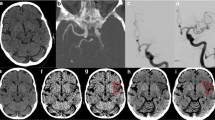

Example of ischaemic lesions in the caudate nucleus (violet arrow) and putamen (blue arrow) in the BW (A), VNC (B) and EM (C) series. In the BW (A) and VNC (B) series, the lesions are not clearly visible, however in the EM the hypodense infarctions can be clearly identified. Follow-up CT with infarction delineation (D)

The follow-up (FU) image evaluation was performed by two experienced neuroradiologists (AEG and TD). Infarctions were assessed by analysing FU imaging (Figs. 1 and 2), performed within a mean of 24 ± 4 h after treatment, which either was a standard CT (n = 32) or an MRI with diffusion- and susceptibility-weighted imaging (SWI) sequences (n = 14). With knowledge of the identified infarctions, density region-of-interest (ROI) measurements were performed on the different reconstructed DE series using the in-house picture archiving and communication system (PACS; IMPAX EE R20 XIV v2014, Agfa, Mortsel, Belgium) and a dedicated workstation. Three ROIs (diameter range: 5–10 mm) were placed in one (up to four) distinct infarction area per patient and in the corresponding contralateral areas. To avoid displacement, ROIs were positioned on the BW series by comparing the FU series and copied electronically on all other series. From the mean tissue densities, contralateral side to infarction differences (CIDs) were calculated for each series as an objective marker for the contrast between the two tissues. Infarction volumes in all reconstructed DE series and the follow-up imaging were measured using a 3D post-processing workstation (Advantage Workstation 4.6/VolumeShare 5; General Electric Company; Fairfield, CT, USA) by two experienced neuroradiologists (TD and BG). To do this, the series was digitally transferred to the workstation. The infarction was circumnavigated in axial planes using a marking tool. Once marked in all slices, the object was cut out throughout all slices by a ‘scissors tool’, keeping the selected parts of the volume. After this, another tool can be applied to determine the volume of the selected infarction.

The lowest infarction densities were found in the EM series (1.6 ± 14.1 HU), followed by the VNC series (25.4 ± 3.1 HU), and the BW series (37.5 ± 3.5 HU). The highest CIDs were displayed with the EM series (73.3 ± 49.3 HU), higher than with the VNC series (8.3 ± 4.7 HU) and the BW series (-1.72 ± 13.3 HU). In the EM series, the peripheral infarction density (8.67 ± 26.13 HU) was higher than the infratentorial infarction density (-2.72 ± 50.07 HU) and density of the central infarctions (-4.44 ± 57.59 HU; p = 0.628). The inter-rater agreement of the density measurements and infarction volumetrics was excellent (Table 1).

Rater 1 identified 99 (90.0%) and rater 2 identified 100 (90.9%) of the overall 110 infarctions present in the EM series in the early stage after endovascular therapy, significantly more than using the VNC or BW series (chi-square test, p < 0.01). The detectability of the infarctions was statistically independent from the localisation of the infarction: rater 1 identified 44 of 46 deep cerebral infarctions and 44 of 49 superficial infarctions in the EM series; rater 2 identified 45 of 46 deep cerebral infarctions and 44 of 49 superficial infarctions in the EM series. Furthermore, rater 1 identified 88 of the 95 supratentorial and 11 of 15 infratentorial infarctions in the EM series; rater 2 identified 89 of 95 of supratentorial and 11 of 15 infratentorial infarctions in the EM series.